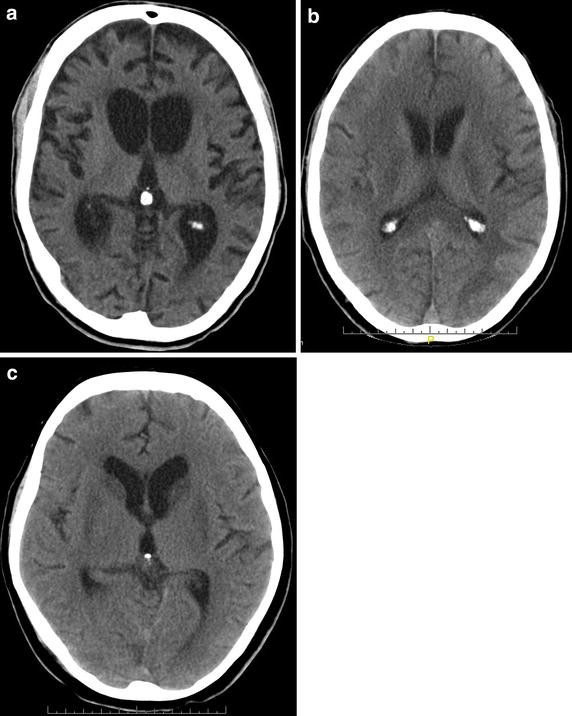

Get Brain Injury Ct Scan US. Brain scans are usually not helpful for a concussion. A ct scan can quickly visualize fractures and uncover evidence of bleeding in the brain (hemorrhage), blood clots (hematomas), bruised brain tissue (contusions).

'brain windows' are used to view a range of densities close to the average density of the soft tissues of the. A ct scan can show potential fractures and can detail haemorrhages and haematomas in the brain, as well as contusions and swelling. A ct scan takes pictures to create images of the brain. In an emergency, it can show internal injuries and bleeding quickly.